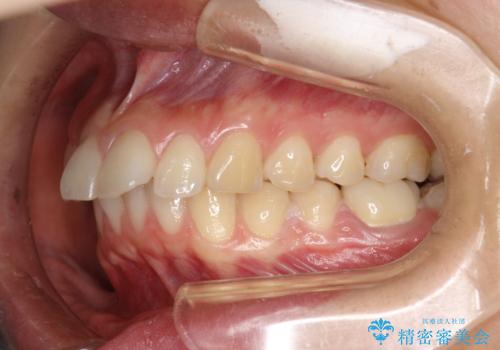

矯正後の後戻りで前歯にガタツキができてしまった インビザラインで改善

- 子どものときにワイヤー矯正をしていたが、後戻りによって前歯のガタツキが気になってきたとのことで来院されました。

アライナー矯正希望だったため、インビザラインによる治療を行いました。

- 7ヶ月